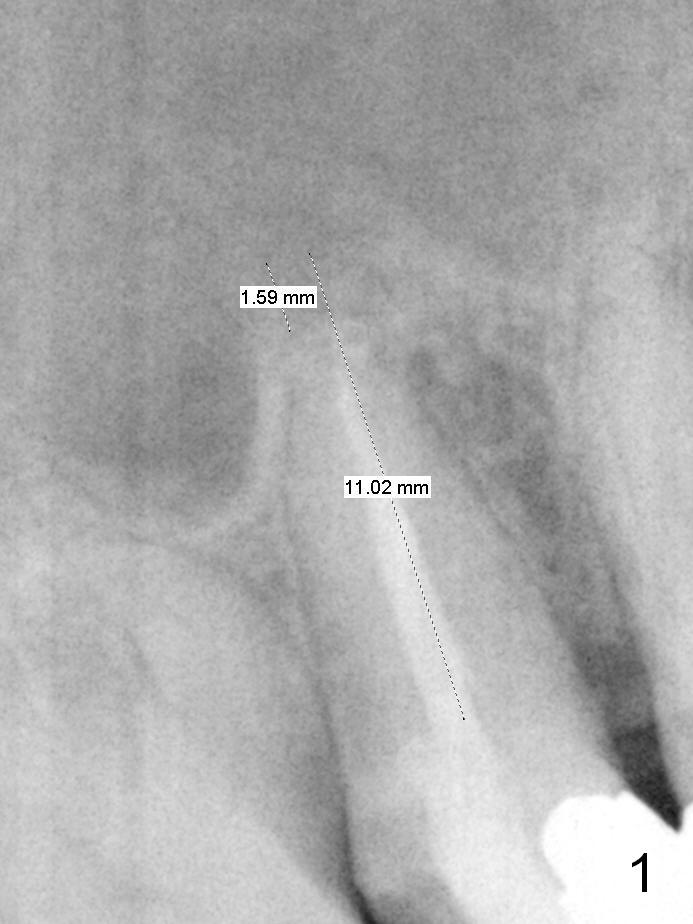

To prevent sinus lift related sinusitis, a shorter implant is going to be placed (Fig.1), approximately 2 mm beyond the apex.  Following extraction, the buccal plate (Fig.3a (coronal section): B) is not only ~ 2 mm shorter than the palatal one (P), but also thinner.  Since the bone density of the palatal plate is higher, without osteotomy an implant is less likely placed in the middle of the socket (S (Fig.1); Fig.3b) than buccal (Fig.3c).  Therefore drills are used to form osteotomy in the apical 1/3 of the palatal slope (Fig.3d (red arrow); SM: sinus membrane).  When 3.3 mm Magic Drill (MD) is in place (Fig.2), the distal surface of the sinus septum is perforated without air leakage.  Demineralized allograft (.0125-.085) is placed for sinus lift (Fig.4 *) prior to placement of 4.5x11 mm implant with ~ 30 Ncm.  The implant is slightly buccal to the ideal position indicated in Fig.3e (curved blue line: sinus lift).  A 4.5x4(2) mm pair abutment is placed for an immediate provisional to hold mineralized allograft in the remaining socket gaps (Fig.4 arrowheads, .5-1.5 mm).  A 9 mm implant may avoid sinus floor perforation on the distal slope of the 2nd premolar.  The osteotomy should have been established initially as mesial as possible.  In fact the patient has nasal hemorrhage while sneezing for the first 2 days postop.  Although he complains of pain buccal to the implant, the gingiva appears to heal 7 days postop (Fig.5).  The distobuccal papilla appears to be displaced somewhat.  Raising mucoperiosteal flap is most likely associated with postop pain and esthetic compromise.  The implant appears to have osteointegrated 5 months postop (Fig.6).  A 4.5 mmx15° 3 mm cuff angled abutment is placed for final restoration.  The distolingual portion of the implant is supported by the regenerated bone 3 years post cementation (Fig.7,8).  There is no bone loss 4 years 2 months post cementation (Fig.9,10).